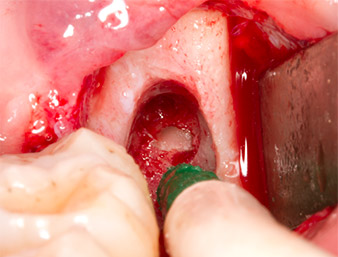

Pour exposer le reste radiculaire en minimisant le traumatisme causé aux tissus, un autre insert est utilisé (Piezomed S2) qui est principalement indiqué pour la préparation de la fenêtre latérale dans les élévations de plancher sinusien. La boule diamantée est également utilisée pour adoucir les bords osseux tranchants (Fig. 6 et 7). Tous les inserts Piezomed sont utilisés avec le paramétrage par défaut automatique, et sans la fonction Booster.

Piezomed S2

Fig. 6 : Le reste radiculaire est soigneusement exposé à l’aide d’un insert sphérique diamanté (Piezomed S2), les arêtes osseuses sont adoucies.

Reste radiculaire 38

Fig. 7 : Le reste radiculaire 38 (LL8) est bien exposé dans son alvéole en vue de son extraction ultérieure.